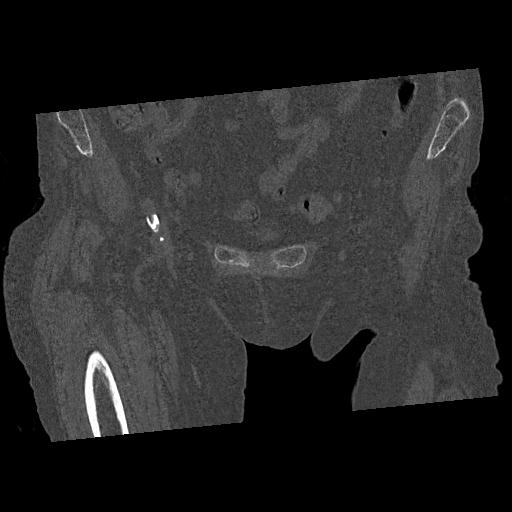

102903 股関節 2R 1/28 +股関節 2R 1/29 78歳女性 左人工骨頭

100703 1/27 両股正面+軸 1/29 両股正面+軸 94歳女性 パンソンロン

46666 1/28 両股正面+軸と 1/26 右手関節 2R 76歳女性 右転子部骨折

37 1/18 両股正面+軸 1/22 2R 86歳女性 右転子下

82084 1/14 1/20 股関節 2R 78歳男性 右人工骨頭

102811 1/13 股関節 2R 1/19 2R 80歳女性 右DHS

91569 3/25 両股正面とラウエン 70歳女性 人工骨頭+バンクーバー